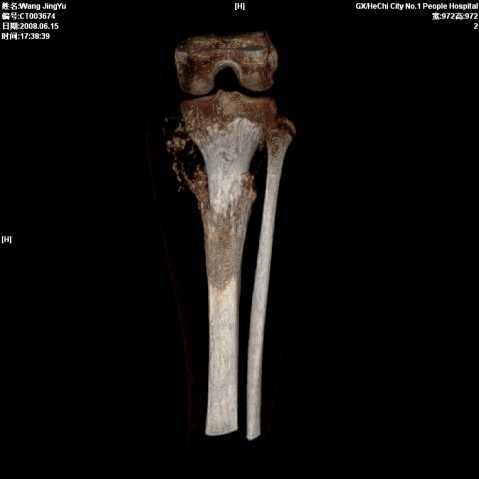

以下是引用随光逐影在2008-6-23 15:30:00的发言:[br]胫骨中上段骨肉瘤(临床表现:好发年龄+好发部位。ct表现:骨质破坏+肿瘤新生骨+骨膜反应并破坏,形成codman氏三角+软组织肿块)。